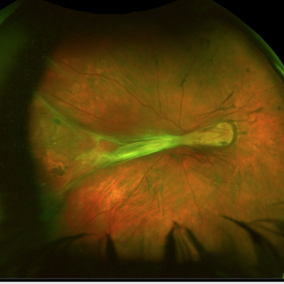

Stage 4a ROP

Stage 4a retinopathy of prematurity in a 6-month-old baby previously treated with laser and intravitreal Avastin.

Photographer: Alexandre Grandinetti

Condition/keywords: retinopathy of prematurity (ROP), vitrectomy